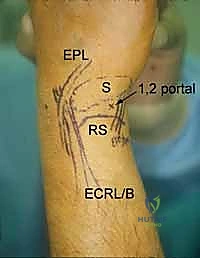

5. The 1-2 Portal

- Location: This portal lies between the first and second dorsal extensor compartments.

- Anatomy:

- First Compartment: Contains the abductor pollicis longus (APL) and extensor pollicis brevis (EPB) tendons.

- Second Compartment: Contains the extensor carpi radialis longus (ECRL) and extensor carpi radialis brevis (ECRB) tendons.

- Neurovascular Risks: The superficial radial nerve (SRN) is highly vulnerable in this region. Its branches can be quite variable. Meticulous blunt dissection and careful palpation of the tendons are crucial.

- Function: Used less frequently than 3-4 or 4-5, but provides an excellent view for radial styloidectomy, visualizing the radioscaphoid joint, and addressing specific pathologies on the radial side.